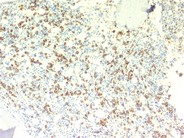

HIV-related plasmacytosis - 3.

On closer examination, there appears to be a marked increase in plasma cells without evidence of atypia as illustrated in this image. Many of these cells appear to be perivascular inlocation. However, there is no associated lymphocyte population, as is normally seen around blood vessels.